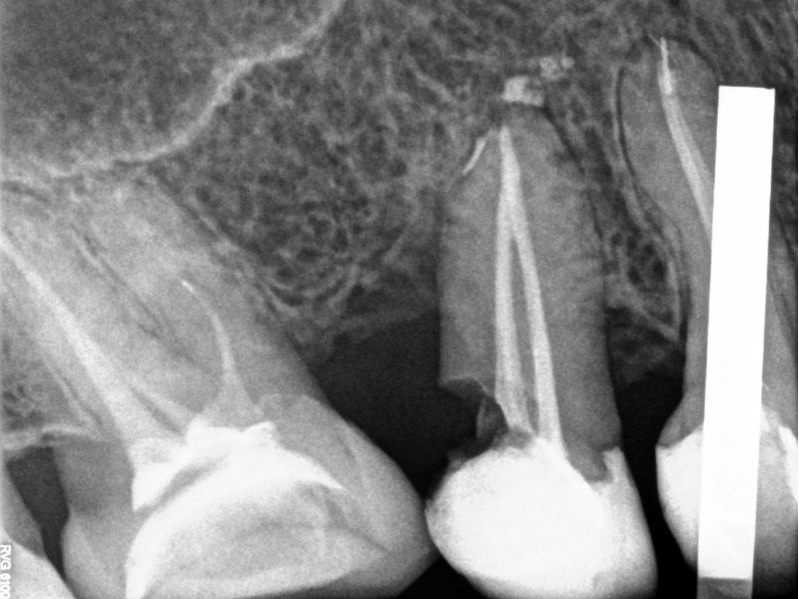

Bogata w płytki i leukocyty fibryna jest stosowana w regeneracji tkanek od ponad 15 lat. Pozytywny wpływ PRF (platelet-rich fibrin) na regenerację tkanek miękkich jest niewątpliwy, bezsporny i częściowo udowodniony w badaniach klinicznych i analizach biochemicznych. Wpływ PRF na regenerację tkanki kostnej jest obserwowany klinicznie, ale nadal niedostatecznie poznany jest mechanizm tego zjawiska.

Platelet- and leukocyte-rich-fibrin has been used in regeneration of tissue for more than 15 years. The positive influence of PRF on the regeneration of soft tissue is undoubtedly, without question and partially proven in clinical studies and biochemical analysis. Influence of PRF on regeneration of bone tissue is observed clinically but the mechanism of this phenomenon is still not sufficiently known.